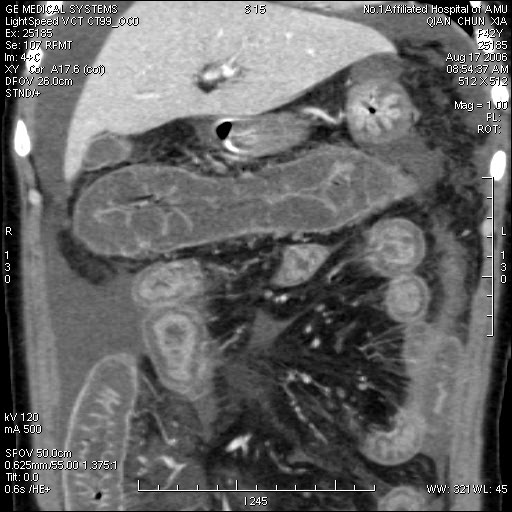

女,42岁,既往体健,近一月来无明显诱因下出现恶心呕吐,同时出现腹泻,否认有结核病,糖尿病史,入院后检查,胸片未见明显异常,ppd阴性,肝转氨酶正常,腹水检查,在漏出液与渗出液之间,胃镜慢性浅表性胃炎,盆腔b超.盆腔积液.

平扫一部分图片

真是少见!至少本人从未见过!整个消化道除了胃壁以外整套小肠及结肠肠壁均不同程度增厚水肿,肠壁间未见积气,亦未见明显的血运障碍(肠细膜上动静脉均显示很好)。盆腹腔积液。

真是少见!至少本人从未见过!整个消化道除了胃壁以外整套小肠及结肠肠壁均不同程度增厚水肿,增强明显分层[粘膜层及浆膜层明显强化,粘膜下层强化轻]。结合病史考虑肠道缺血改变[病因待查--血管炎,结缔组织疾病等]

真是少见!至少本人从未见过!整个消化道除了胃壁以外整套小肠及结肠肠壁均不同程度环形增厚,肠壁密度均匀呈“晕圈”样改变,粘膜下层低密度,粘膜层和外层为相对高密度。增强强化不明显。结合病史考虑肠道急性缺血改变。腹水。形成原因肠系膜动脉栓塞、还是静脉血栓形成看不懂。

真是少见!我也从未见过!整个消化道除了胃壁以外整套小肠及结肠肠壁均不同程度同心圆样增厚,肠壁密度均匀呈“晕圈”样改变,粘膜下层低密度,粘膜层和外层为相对高密度;增强强化不明显。腹腔各个间隙内液性密度积液影,结合病史考虑:肠道慢性中毒性改变(药物性中毒可能性大)。腹水形成原因?

本例ct表现是肠道的整体性充血、水肿,以结肠特别是横结肠、升结肠、盲肠为显著,横结肠一眼粗略看过去,极似极度水肿之胰腺。回肠末段亦呈明显近似结肠改变,小肠则以充血为主,水肿相对轻微。诸段肠管无明显如溃疡、出血等局部损害,重度腹水。肝脏体积变小,肝裂增宽,以肝圆韧带为明显。肝脏各部比例尚正常,无局部外突或内凹,密度均匀一致。胆囊增大,所给图片及楼主已经仔细观察过,肝段下腔静脉肠系膜静脉均正常。